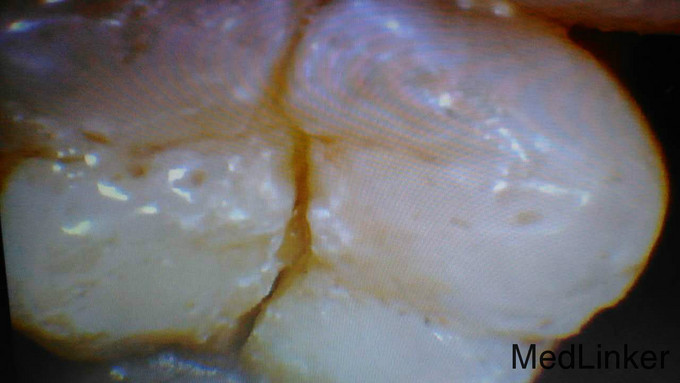

患牙拔除

主诉:右下后牙胀痛一周余。 病史:右下后牙牙龈肿痛一周伴局部红肿发热口服要物无效,前来就诊